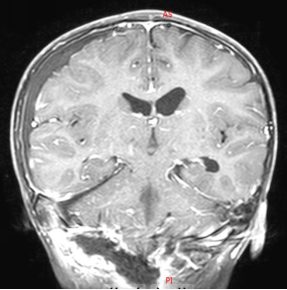

通常情况下,小孩子很少打鼾(俗称打呼噜),如果您的宝宝睡觉打鼾,并且声音很大,那要引起注意了,最好带孩子做个检查,因为睡觉打鼾也有可能是脑肿瘤引起的。